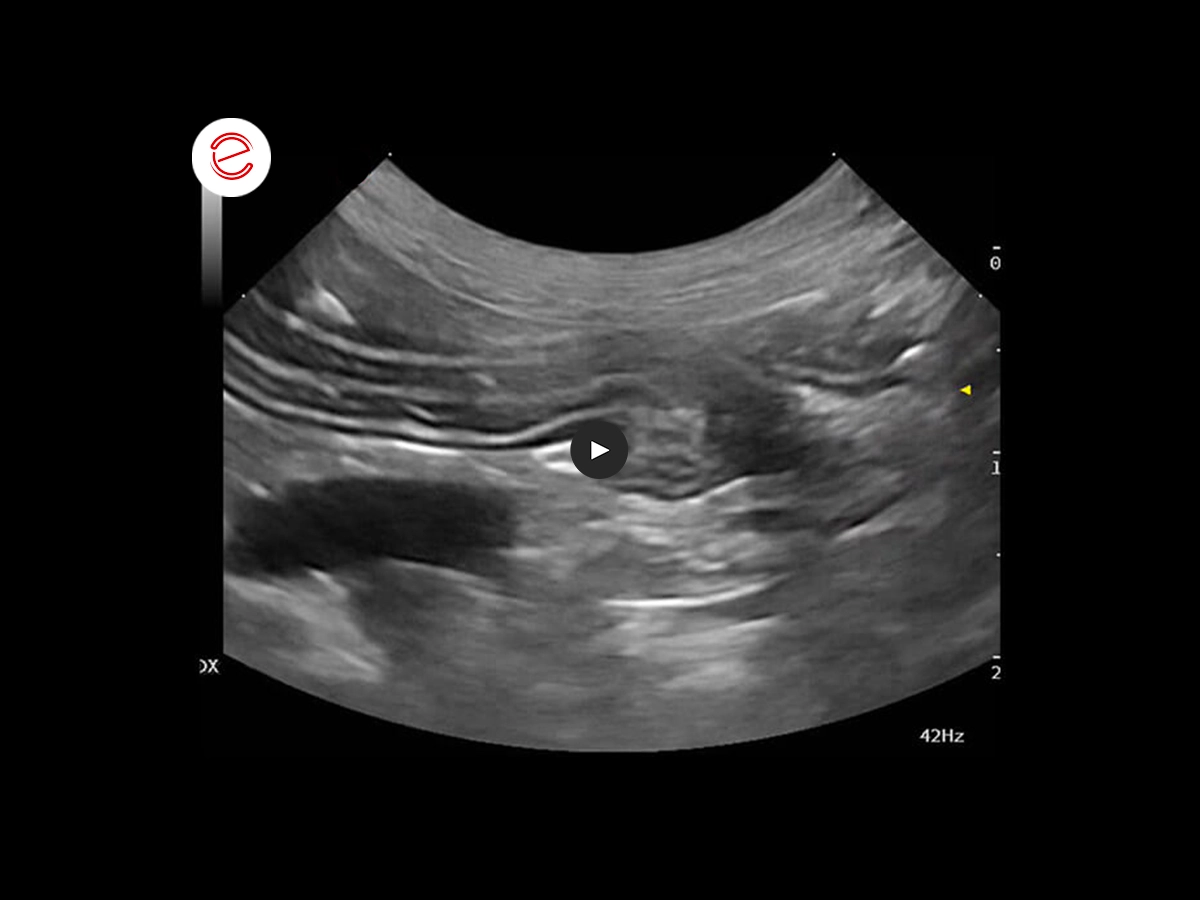

Ecografia dell'intestino

È stata eseguita un'ecografia addominale completa che mostra, tra gli altri risultati, un'anomalia dell'intestino tenue.

Nell'immagine ecografica si può apprezzare la stratigrafia dell'ansa digiunale, che presenta un'anomalia.

- All'esame ecografico, d'altra parte, nel soggetto si osserva uno strato soprannumerario. Le ipotesi avanzate a giustificazione degli strati digiunali soprannumerari, in ordine di possibilità, sono:

- infiltrazione/edema della mucosa

- infiltrazione/edema della sottomucosa

- banda iperecogena che divide le fasce dei muscoli longitudinali da quelle dei muscoli circolari.

Quando i sintomi si risolvono, il reperto scompare.